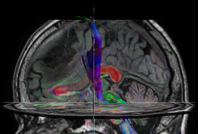

Comprehensive Brain with MultiBand SENSE DTI

-